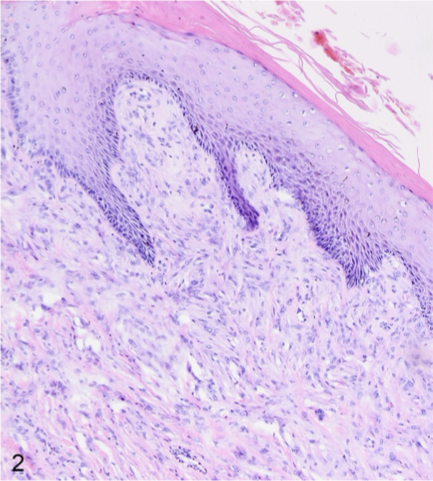

Define papilloma

1-2 cm wart-like, filiform (long, thin, hair-like), exophytic (raised), and hyperkeratotic mass composed of hyperplastic epidermis supported by dermal stalks

What is the difference between viral and non viral papillomas?

Viral

Younger animal

Mass can wane away, stay stable or progresses to squamous cell carcinoma

Presence of koilocytes = abnormal squamous ep. cells, enlarged nucleus (cytopathic effect)